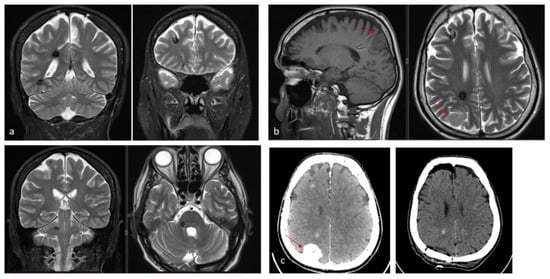

| Lesion Type | MRI Signal | Pathologic Features | Images |

|---|---|---|---|

| Type I | T1: hyperintense core T2: hyper- or hypointense core with surrounding hypointense rim | Subacute hemorrhage surrounded by a rim of hemosiderin-stained macrophages and gliotic brain | ![]() |

| Type II | T1: reticulated mixed signal core T2: reticulated mixed signal core with surrounding hypointense rim resulting in the “popcorn” appearance GE: low signal rim with blooming | Loculated area of hemorrhage and thrombosis of varying age, surrounded by gliotic, hemosiderin-stained brain; in large lesions, areas of calcification may be seen | ![]() |

| Type III | T1: iso- or hypointense T2: hypointense with a hypointense rim that magnifies the size of the lesion GE: hypointense with greater magnification than T2 | Chronic resolved hemorrhage, with hemosiderin staining within and around the lesion | ![]() |

| Type IV | T1: poorly seen or not visualized at all T2: poorly seen or not visualized at all GE: punctate hypointense lesions | Thought to be capillary telangiectasias | ![]() |